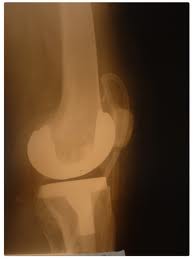

imagesТази малко известна терапия лекува болни стави дори тогава, когато другите начини за лечение са били неуспешни. Реконструктивната терапия всъщност изгражда нови стави, връзки и сухожилия.

Костите и мускулите ни могат да окажат натиск върху връзките, сухожилията и хрущялите, в резултат на което се повреждат ставите на коленете, глезените, шията китките и лактите, както и гръбначният стълб. Някои хора се раждат със слаби стави, които са отпуснати и нестабилни, прекалено подвижни или подвижни и в двете посоки. Реконструктивната терапия помага за коригиране на тези недостатъци. Връзките стават по-дълги, по-здрави и по-притегнати до костта.

По време на лечението в ставата се инжектират ниски дози хранителни вещества. Техният състав се определя в зависимост от нуждите й. Те стимулират леко дразнене. В областта се появяват нови кръвоносни съдове. Повече кръв означава повече кислород и повече хранителни вещества. Тъканите се лекуват, като растежният фибробластен фактор поставя повече фибробласти и колаген във връзките, сухожилията и хрущяла. В резултат на това връзките се заздравяват и по-добре държат прешлените и ставите. Това, от своя страна, елиминира болката.